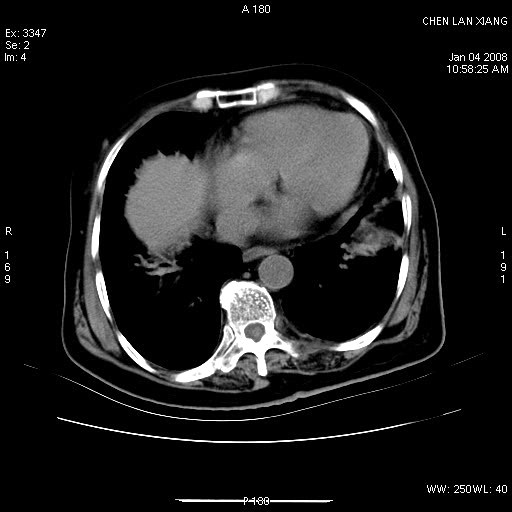

女,76岁,腹痛3-4天,b超示:肝内实性肿物,胆囊强回声,胆总管扩张.

考虑:1、胆总管下端结石伴梗阻性肝内外胆管扩张(肝左叶外侧段肝内胆管多发结石、胆管炎);

2、肿囊癌累及肝,不除外 黄色肉芽肿性胆囊炎。

1 胆总管末端结石伴肝内胆管结石,肝内外胆管扩张。2 胆囊扩大,胆囊壁不规则增厚,内见软组织密度影。考虑:慢性胆囊炎,不除外胆囊癌!

标题: 肝右叶病灶

胆囊癌侵犯肝右叶?

1)胆囊癌伴肝脏转移。2)胆总管下端结石、肝内胆管结石伴肝内外胆管扩张。